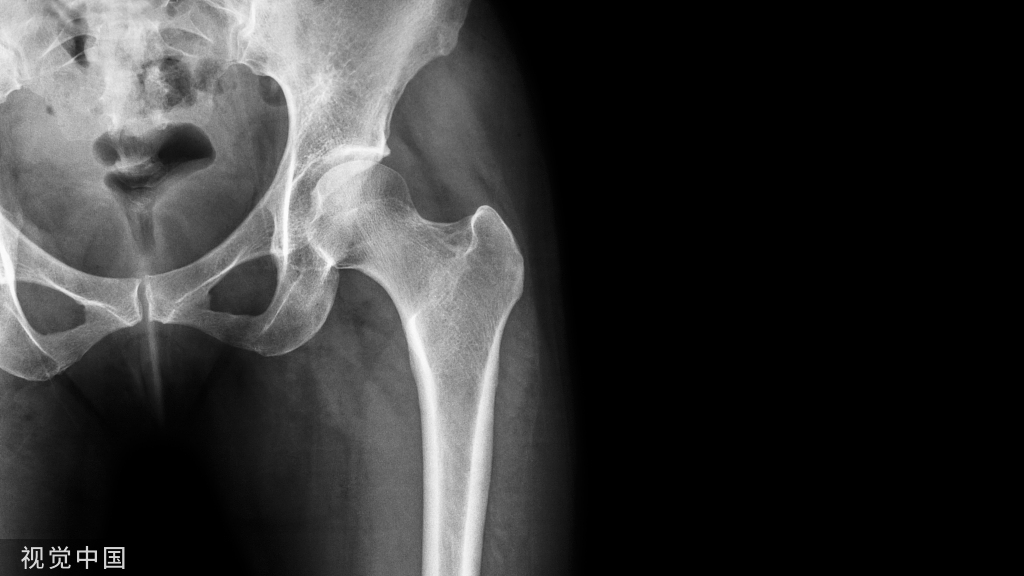

X线读片是骨科医生的基本功。

今天是腕部与手的X线片。所有X线片都

带有标注和说明

,可以选择长按图片,

自动翻译相关说明

。

进阶篇